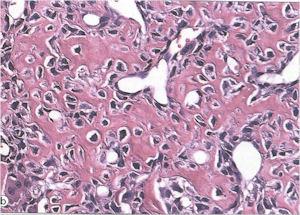

Aggressive Osteoblastoma

- Aggressive osteoblastoma is a distinct rare type of osteoblastoma that has a much more aggressive local behavior than a conventional osteoblastoma. They have a higher chance for local recurrence after removal.

- There has been controversy about the true existence of this type of tumor and whether these tumors are actually low grade osteosarcomas.

- They have a similar appearance microscopically as a conventional osteoblastoma except the osteoblasts are twice as large and have an epithelioid quality with abundant eosinophilic cytoplasm (Epithelioid Osteoblasts).

- Aggressive osteoblastoma is a borderline lesion lesion between osteoblastoma and osteosarcoma. It is not a precursor to osteosarcoma. It does not metastasize.

- Aggressive osteoblastomas usually occur in an older age group than conventional osteoblastoma.

- Most patients are older than age 30. It affects a broad variety of bones.

- Aggressive osteoblastomas are usually larger than a conventional osteoblastoma and have been reported to be up to 8.5 cm in diameter.